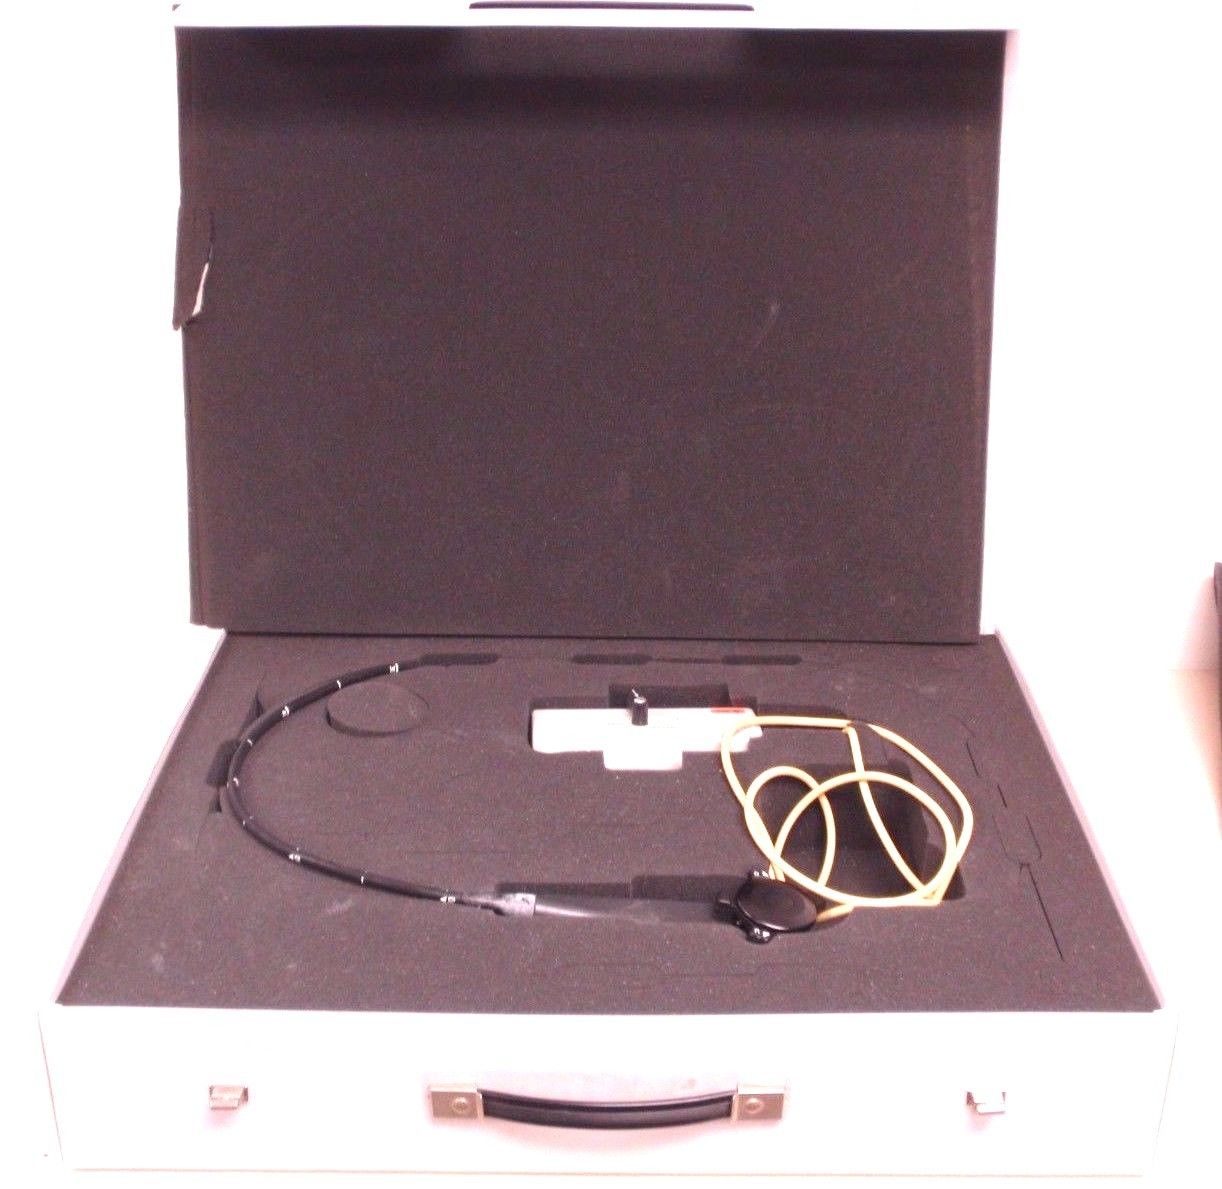

DIAGNOSTIC ULTRASOUND MACHINES FOR SALE

Aloka SSD-1000 Ultrasound With 3.5Mhz Probe

Sale price$ 2,399.30